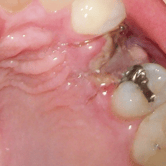

Infección postoperatoria

La infección postoperatoria puede ocurrir después de una cirugía maxilofacial, manifestándose con dolor, hinchazón, fiebre y supuración.

Los pacientes deben estar atentos a estos signos después de la cirugía.

El tratamiento incluye antibióticos y, en algunos casos, la limpieza quirúrgica del área afectada.